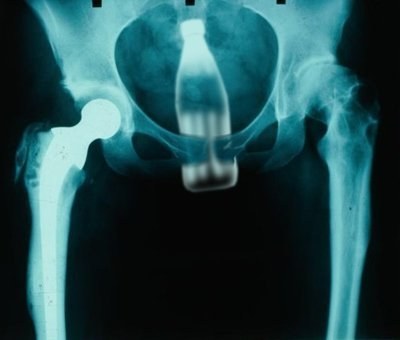

13. Ένα μπουκάλι κοκα κόλας!